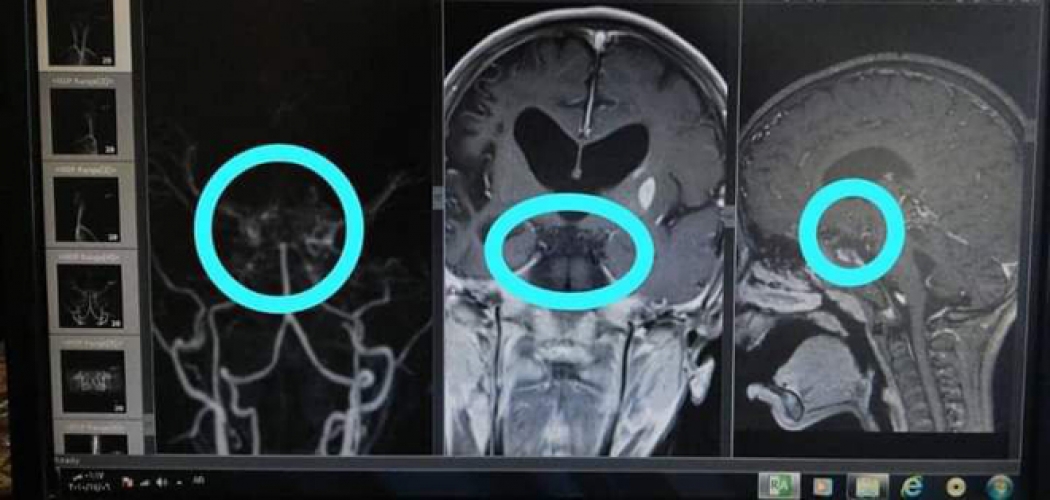

ووفق الدكتور الرمحين وهو مشرف بشعبة الجراحة العصبية بمشفى الأسد الجامعي بدمشق أن أجراء صورة رنين مغناطيسي للدماغ والشرايين والأوردة مع حقن مادة ظليلة وتخطيط للدماغ إضافة إلى تحاليل مخبرية شاملة أثبتت تشخيص إصابة الطفلة بمرض “مويا مويا”، وهو مرض نادر جداً يصيب العرق الصيني والياباني، حيث أظهر الرنين المغناطيسي وجود علامات شعاعية مميزة لهذا المرض وحدوث انسداد في الشريان السباتي الداخلي المغذي للدماغ بالجهتين.